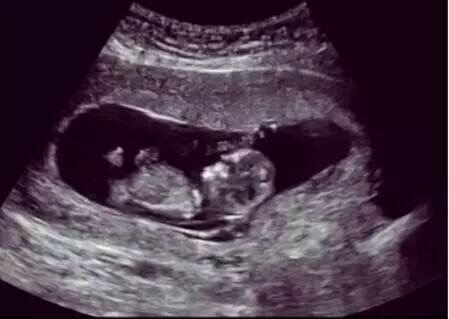

那超声波对胎儿有害吗?

超声波使用的是一种声波,不是离子射线。目前为止,从没有过诊断性超声波造成胎儿损伤的报道出现,包括多普勒彩超。孕期超声波是不受威胁的,这也是为什么现代妇产科产检不用x线,而常规用超声波。